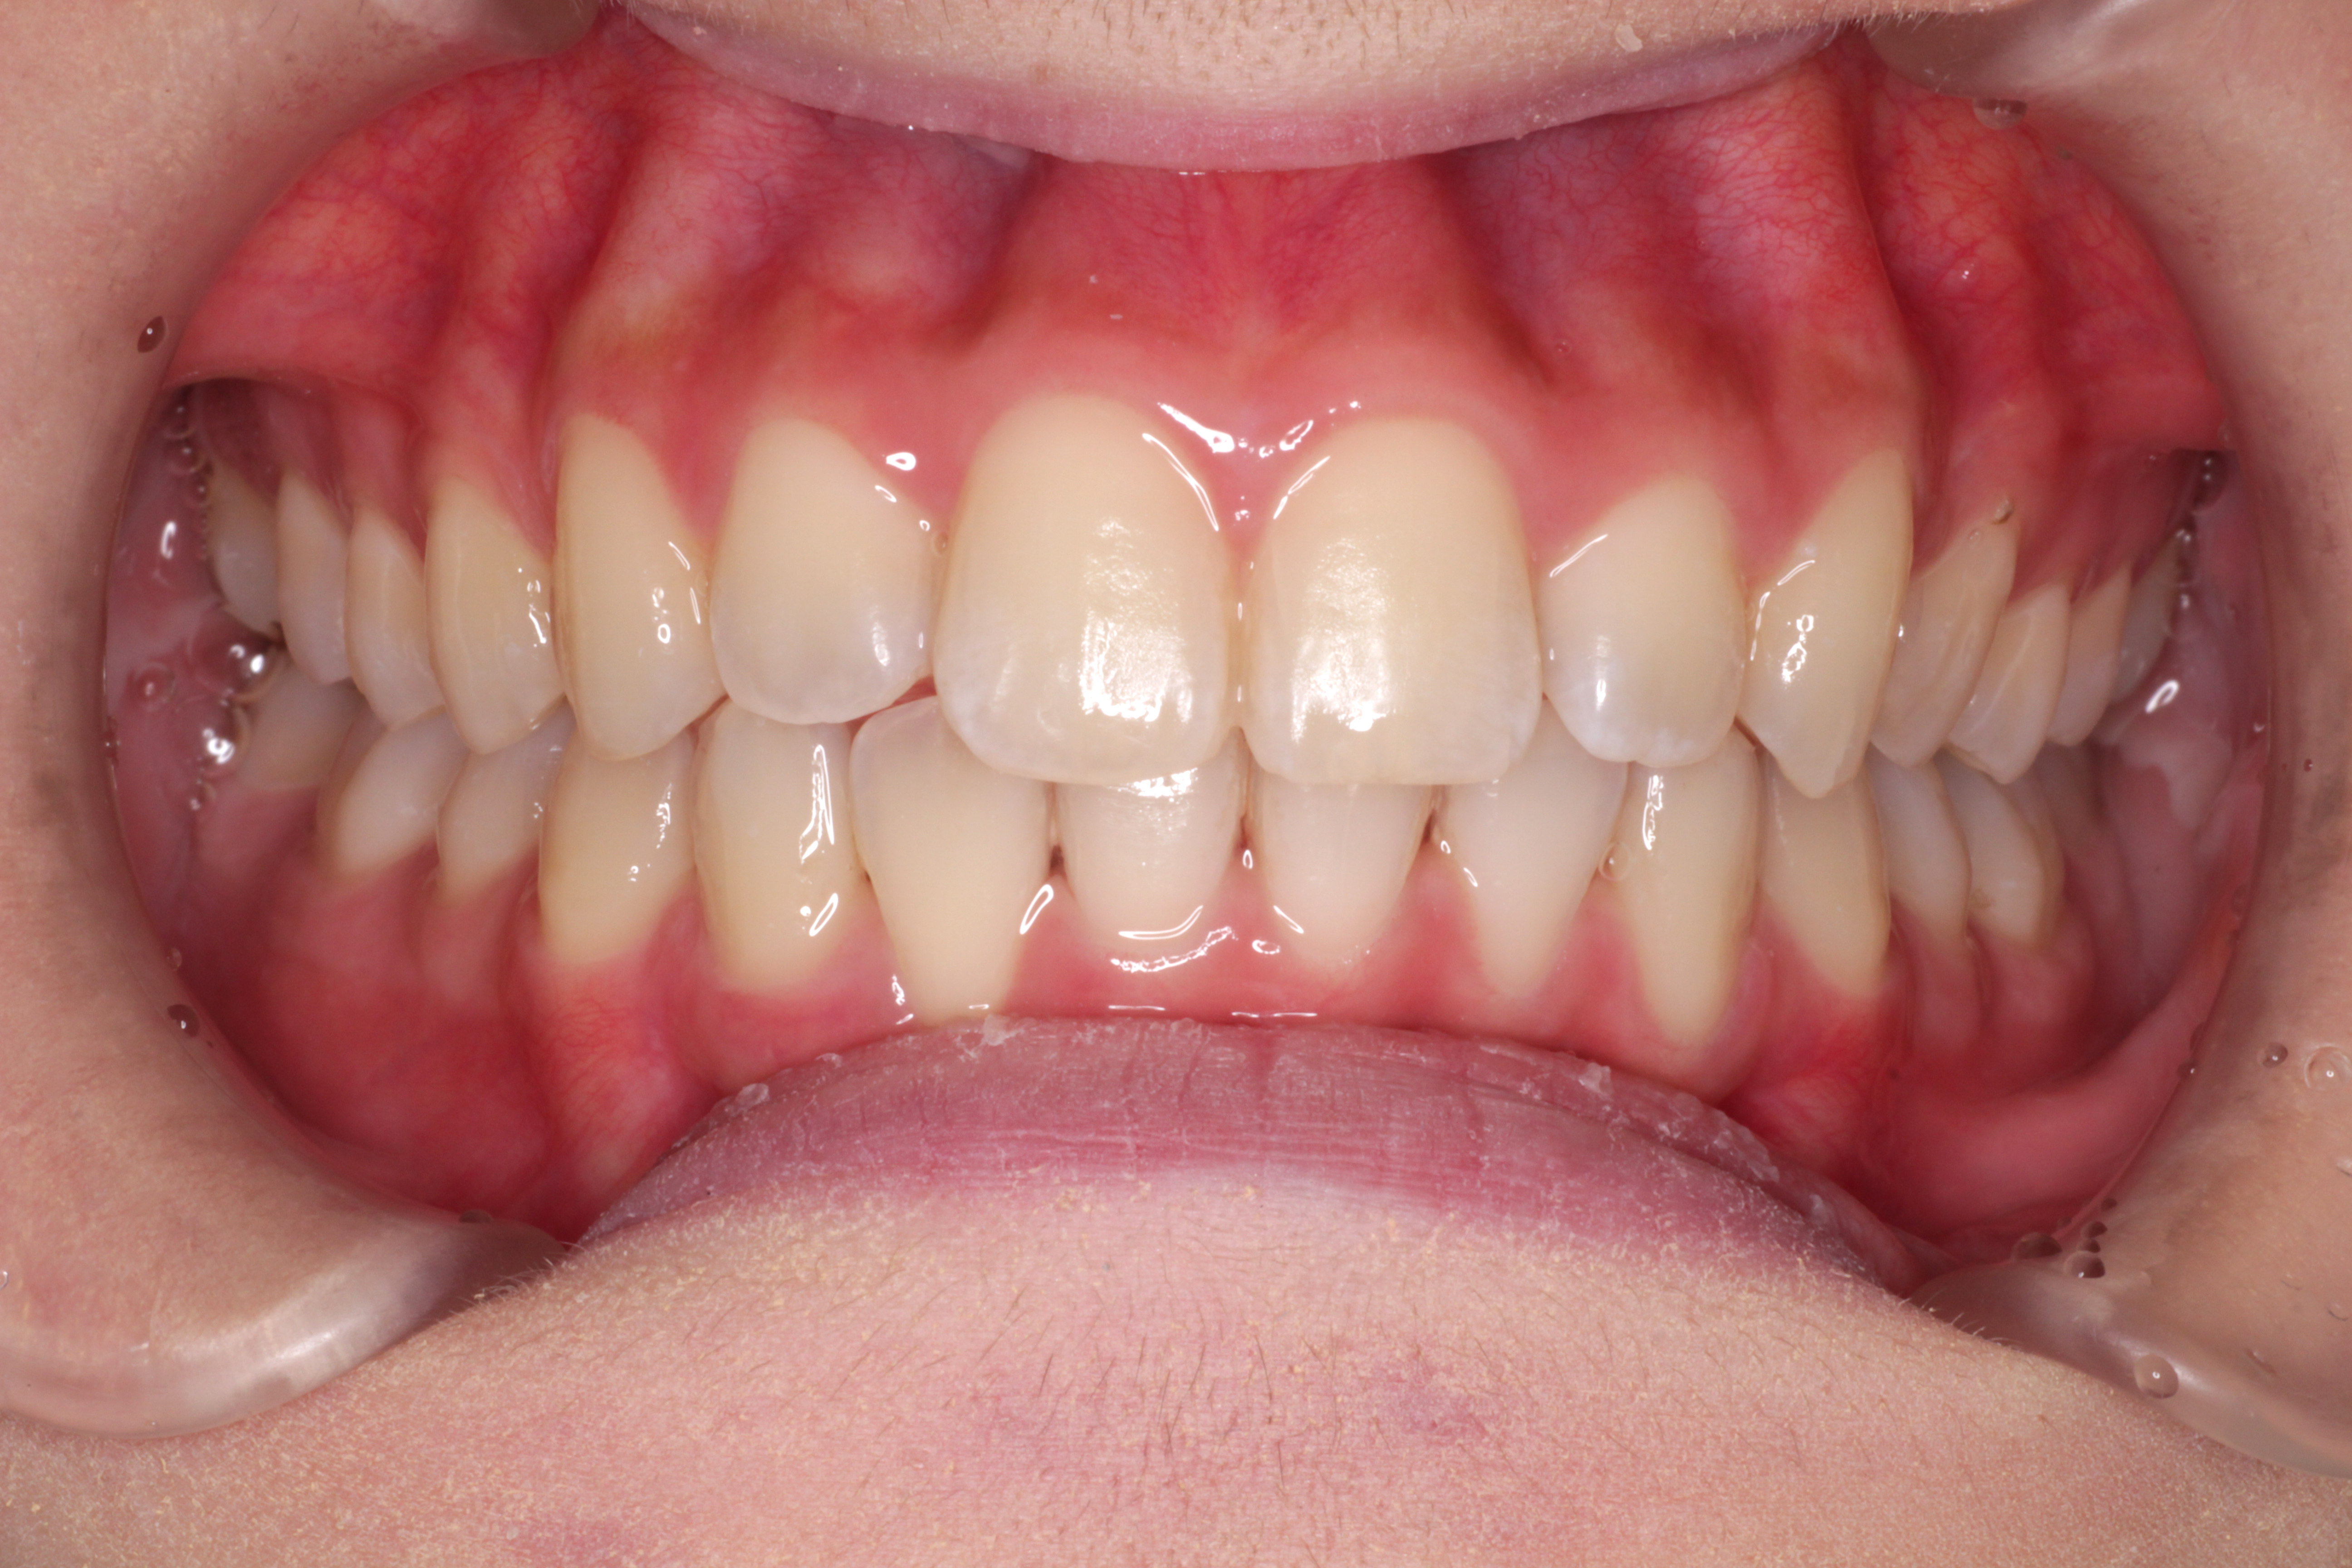

初診時のお口の中の状態です。↓

お口の中の状態としては

⑴咬み合わせが深い。(上の歯がかぶさっていて、下の歯が見えません。)

⑵右下の前から2番目の歯が叢生で歯列に入っていません。

⑶右上の前から2番目の歯が下の歯より前にありません。

診断:上顎前突・前歯部叢生